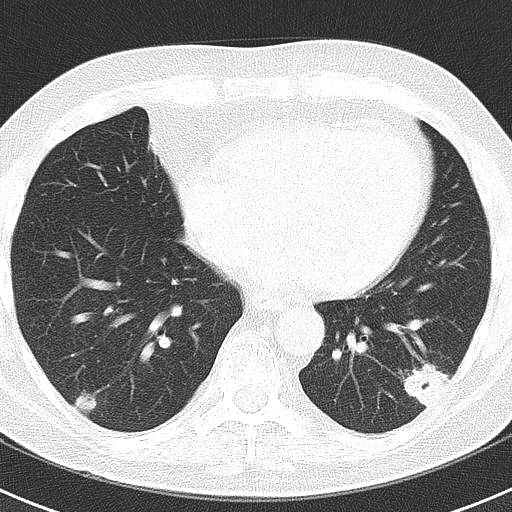

Bronchiale adenomen: Dit zijn goedaardige tumoren die zich ontwikkelen in de bronchiën, de luchtwegen in de longen. Dit is een kleine, ronde groei op de longen die als een witte vlek op beeldscans te zien is

Source: kobidurxb.pages.dev Wat zijn longblaasjes? (Hoe werken de longen) YouTube , Op röntgenfoto's of scans kunnen deze gezwellen eruitzien als een schaduw of vlek op de long Dit is een kleine, ronde groei op de longen die als een witte vlek op beeldscans te zien is

Source: infoclinvjo.pages.dev Vlekjes op pols Medische Forum Dokter.nl , Intrapulmonale tumoren geven ook witachtige schaduwen op de röntgenfoto van de borstkas.Longkanker is in verschillende landen een van de belangrijkste oorzaken van oncologische sterfte. Hier zijn de mogelijke complicaties: Ademhalingsproblemen.

Source: mausicaljbm.pages.dev Vlekjes op je huid in de zomer? Dan heb je waarschijnlijk dít , Luchtwegaandoeningen en infecties kunnen knobbeltjes in de longen veroorzaken Intrapulmonale tumoren geven ook witachtige schaduwen op de röntgenfoto van de borstkas.Longkanker is in verschillende landen een van de belangrijkste oorzaken van oncologische sterfte.